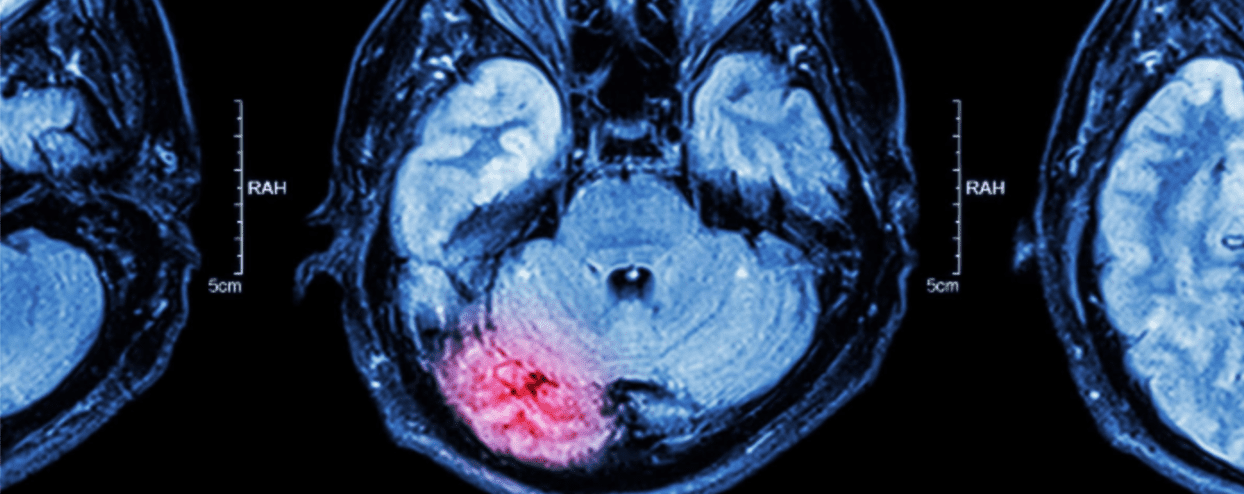

Traumatic brain injuries (TBI) occur from an outside force, and are commonly caused by sports injuries and car accidents. In many cases, symptoms can improve over time with the help of therapy. In some cases, however, it’s possible for symptoms to worsen over time. Here’s a closer look at why some cases improve and others appear to decline.

Secondary Brain Injury: In certain patients, complications develop after the initial injury, such as an infection or hematoma. The injury may also cut off blood to the brain, causing brain cells to die. The effects of these secondary brain injuries may not appear right away, which is why some patients’ symptoms seem to worsen over time.